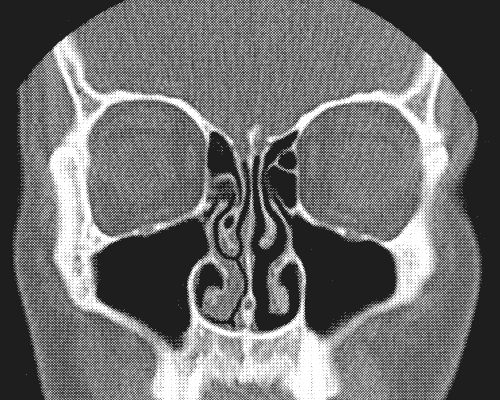

Wendekreis des Septum

Das war anstrengend. Dienstagmorgen 6:45 Einweisung, gegen 8 die OP. Um 9 wieder wach. „Wendekreis des Septum“ weiterlesen

Immer der Nase nach